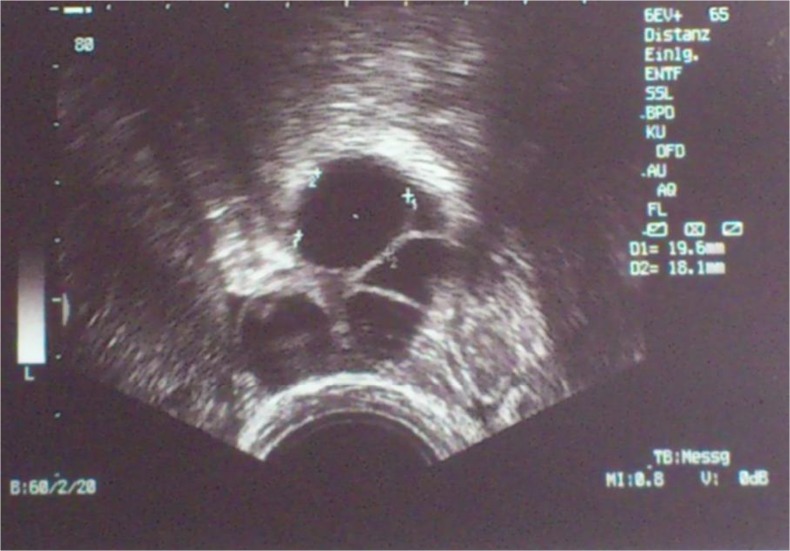

The GnRH agonist flare-up protocol was performed [8] and intranasal GnRHa (Synarela (0,23 mg Nafarlinacetat/0,1 ml): Pfizer, Berlin, Germany) administration twice daily (0,2 ml/d) was started on day 7 after the caesarean delivery. After another 2 days (9 days after the caesarean delivery), human menopausal gonadotropin (hMG, Menogon HP: Ferring, Saint-Prex, Switzerland) administration at 225 IE/day was started. On the eighth day of stimulation, the hMG dosage was increased to 300 IE/day (14 days after the caesarean delivery). On the 14th day of stimulation (20 days after the caesarean delivery), the leading follicle was 18–19 mm in diameter (Fig. 1); hence, ovulation induction using 10.000 IE hCG (Brevactid: Ferring, Saint-Prex, Switzerland) was performed, followed by oocyte retrieval 36 h later. We obtained 4 oocytes in total, of which 2 were metaphase I and the other 2 were used for intracytoplasmic sperm injection. One oocyte (PN, day 2) was fertilised and cryopreserved.

Fig. 1.

Sonogram obtained on the day of induction of ovulation (day 20 after the caesarean delivery)